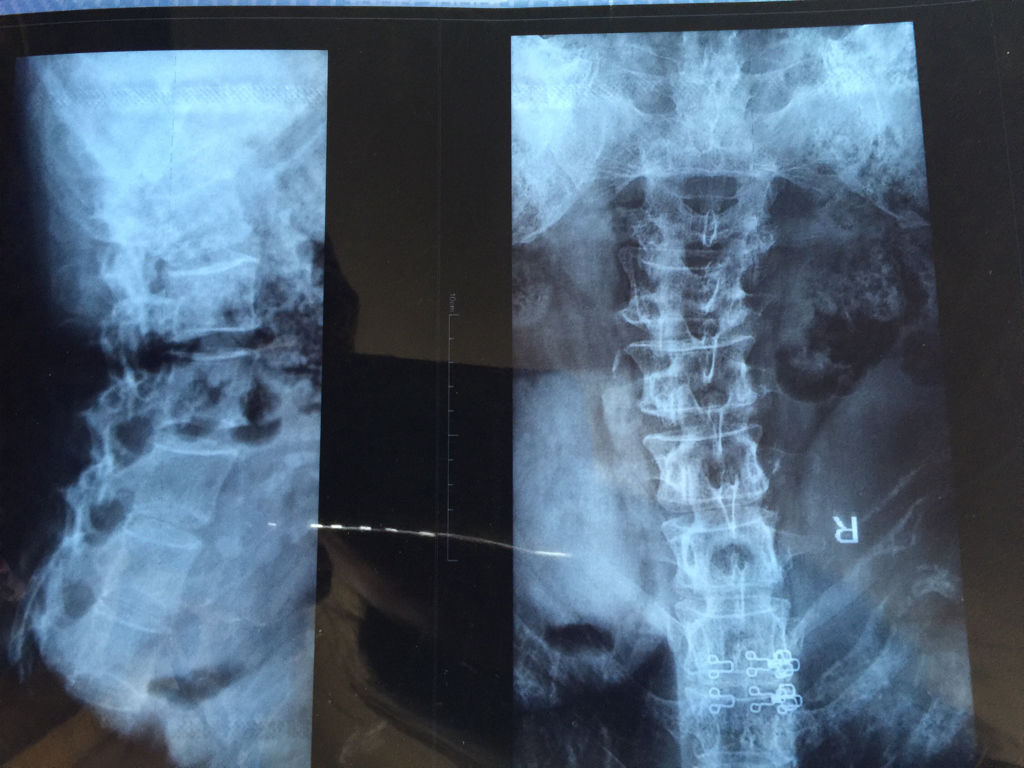

腰椎骨折的微创治疗方法—经皮椎弓根螺钉内固定术_患者